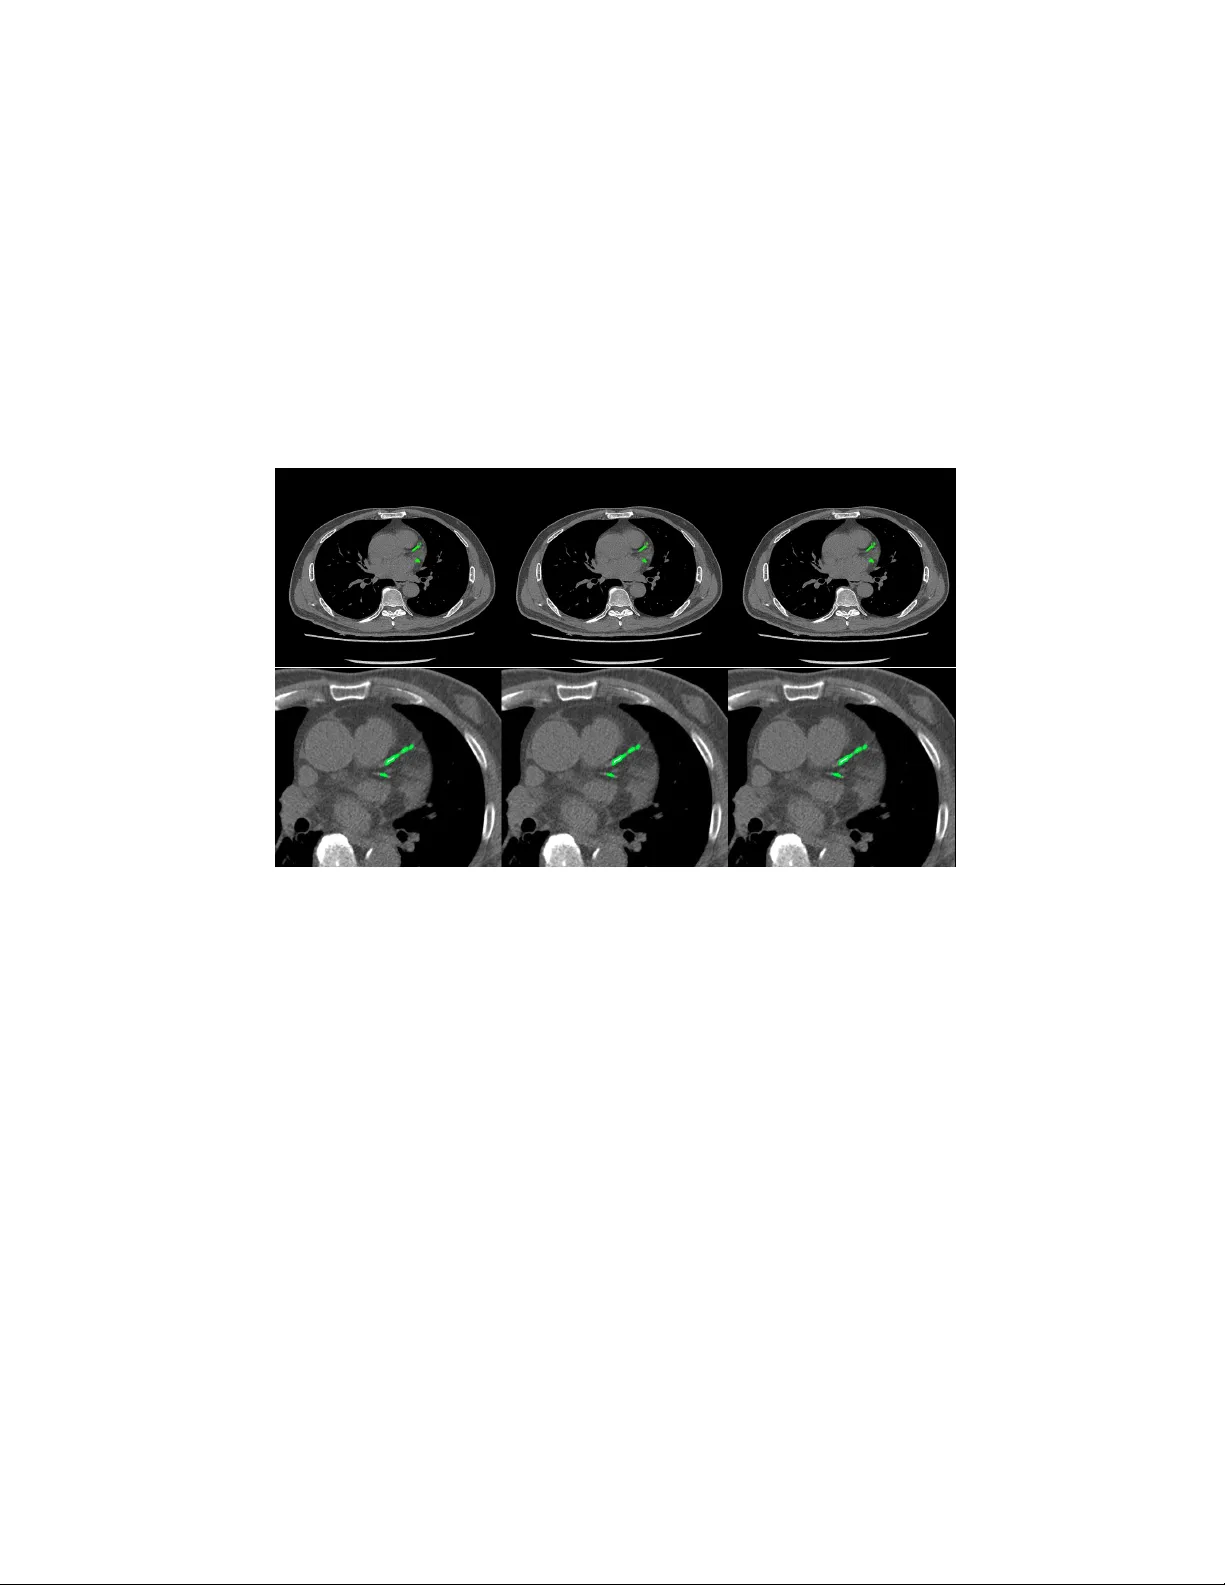

Automatic Calcium Scoring in Cardiac and Chest CT Using DenseRA Unet Jiec hao Ma and Rongguo Zhang Infervision Inc. Abstract. Cardio v ascular disease (CVD) is a common and strong threat to h uman b eings, featuring high prev alence, disabilit y and mortality . The amoun t of coronary artery calcification (CAC) is an effectiv e factor for CVD risk ev aluation. Conv entionally , CAC is quantified using ECG- sync hronized cardiac CT but rarely from general c hest CT scans. How- ev er, compared with ECG-synchronized cardiac CT, chest CT is more prev alen t and economical in clinical practice. T o address this, w e propose an automatic metho d based on Dense U-Net to segmen t coronary calcium pixels on b oth types of CT scans. Our contribution is tw o-fold. First, we prop ose a no vel netw ork called DenseRAUnet, which tak es adv an tage of Dense U-net, ResNet and atrous conv olutions. W e prov e the robustness and generalizabilit y of our mo del by training it exclusively on chest CT while test on both types of CT scans. Second, we design a loss function com bining b ootstrap with IoU function to balance foreground and bac k- ground classes. DenseRAUnet is trained in a 2.5D fashion and tested on a priv ate dataset consisting of 144 scans. Results sho w an F1-score of 0.75, with 0.83 accuracy of predicting cardiov ascular disease risk. Keyw ords: Calcium scoring · deep learning · Cardiac CT · Chest CT · Agatston score · Conv olutional neural net work. 1 In tro duction Cardio v ascular disease (CVD) has b ecome one of the most high-mortalit y dis- eases, for whic h the amount of coronary artery calcification acts as a strong indicator of CVD risk [1]. In clinical practice, CA C is quan tified b y the Agat- ston score, using dedicated cardiac CT scans, follo wed b y a expert who man ually iden tify CA C lesions. T o assist medical professionals, previous w ork based on classical machine learning ha ve attempted to design CAD methods for computation of CAC score. Durlak et al. [2] applied an atlas-based feature approac h in combination with a random forest classifier whic h is used to incorporate fuzzy spatial kno wledge from offline data. Isgum et al. [3] emplo yed a nearest neighbor classifier directly and a tw o-stage classification with nearest neigh b or as well as supp ort v ector mac hine classifiers. There are plent y of other researc h can b e explored [4,5,6]. In recen t years, conv olutional neural net works (CNNs) hav e exhibited great success in Computer Vision by data-driven, esp ecially in image classification 2 Jiec hao Ma and Rongguo Zhang tasks. Mean while, fully con volutional netw orks (FCNs) , as the extension of CNNs, also obtained state-of-the-art p erformance for segmentation problems. In the context of medical image segmentation, sp ecifically cardiac calcification seg- men tation, algorithms based on deep learning ha ve shown promise. W olterink et al. [7] first attempted to apply CNNs to CAC scoring in con trast-enhanced cardiac CT, with a tw o-stage netw ork structure but only one stage using deep learning. Recen tly , some w orks used t wo-stage deep learning structure [8,9], with the first stage identifying CAC-suspected vo xels and the second stage more pre- cisely identifying CAC. Shadmi et al. [10] emplo yed Dense-FCN, a design differ- en t from the tw o-stage methods, to segmen t the lesion directly in cardiac CT. But all the automatic CAC scoring approaches ab o ve are designed for either cardiac or c hest CT only . More recen tly , m ultiple screening in one CT session has b ecome a trend in clinical practice. Huang et al. [11] presented an automatic metho d with t wo CNNs that p erforms direct computation of CAC score in b oth cardiac and chest CT scans. On the other hand, according to the work of W olterink et al. [9], 2.5D input has a great adv antage compared with 3D input in CAC scoring, as the n umber of parameters are greatly reduced while retaining spatial information. Both Lessmann et al. and wolterink et al. [8,9] used the 2.5D Con vNets com- bining features from three identical 2D ConvStac ks with shared w eights, eac h pro cessing an input patc h from a differen t orthogonal viewing direction (axial, sagittal and coronal). T o our kno wledge, none hav e applied the efficien t 2.5D F CN arc hitecture on multiple types of non-enhanced CT. In this w ork, we prop ose an automatic method for CAC scoring on b oth ECG-sync hronized cardiac and chest CT. Unlike the the metho ds required tw o cascaded netw orks to calculate CA C scoring, our net work directly segment the calcified vo xels and obtain CAC scoring. Meanwhile, we adopt a 2.5D patch input to reduce the computational ov erhead of 3D input. Instead of previous 2.5D metho ds [8,9]which input patc h from axial, sagittal and coronal direction, our netw ork tak es 9-channel stacks of images with corresp onding 2D labels for segmen tation of the corresp onding center slice. W e applied our metho d on a priv ate dataset comp osed of 44 Cardiac CT scans and 805 chest CT scans. In comparison to exp erts’ manual annotations, our algorithm achiev ed comp etitive results. 2 Materials and Metho ds 2.1 Data A dataset of 849 CT scans w as collected from several medical cen ters in China, whic h consists of 805 chest CT scans and 44 cardiac CT scans. The CT scans w ere acquired b y different CT scanners with Philips, GE and Siemens. Each CT scan contains a sequence of slices at the thin-section slice spacing (range from 1.0 to 3.0 mm). CAC lesions were manually labe led b y three exp erienced radiologists from differen t cen ters. Automatic Calcium Scoring in Cardiac and Chest CT Using DenseRAUnet 3 W e newly connected 144 CT scans as a test set, incorporating c hest CT scans and cardiac CT scans from medical centers in China. And to ev aluate our net work p erformance, lesions w ere delineated by exp erienced radiologists. 2.2 Data preprocessing Since the connected dataset con tains v arious sizes of chest CT scans and cardiac CT scans, w e process all images as follows. First, w e resize all CT images to 512 × 512 pixel resolution. Second, we randomly crop and then resize images to 512 × 512, where maximum size of the cropped image is 256 × 256. W e con tinuously select nine pro cessed slices as the input of our net work, and for such an input, its lab el is the ground-truth lab el of its middle slice. W e also pro cess all ground- truth lab els to alter the pixel lab el when its corresp onding CT v alue low er than 130HU. 2.3 DenseRA Unet for segmen tation W e prop osed a no vel F CN architecture based on dense U-Net for calcification segmen tation, called DenseRA Unet. The netw ork consists of tw o main comp o- nen ts: (1) a basic netw ork for feature extraction, and (2) three task-specific sub-net work structures, incorporating R esidual A tr ous Unit (RAU) , scSE blo ck and Extr a Dense Blo ck (EDB) . Fig. 1 depicts our prop osed DenseRAUnet. Dense Block 1 Dense Block 2 T Dense Block 3 T Dense Block 4 T upsample block2 upsample block3 !" sample block 1 scSE scSE scSE RAU RAU RAU EDB upsample block Atrous Conv Dilation=2 Atrous Conv Dilation=4 Atrous Conv Dilation=8 BatchNorm BatchNorm BatchNorm ReLU ReLU ReLU Concact + X Identity F(X)+X Residual Atrous Unit Conv Deconv , 3 # 3 Conv , Relu T T ransition Layer Input Output Concat Avg-pooling 2 ×2 Fig. 1. The ov erall structure of DenseUnet and details in Residual Atrous Unit The basic net w ork is an enco der-deco der architecture, similar to dense U-Net. W e adopt a bac kb one netw ork (DenseNet-121) as the enco der sub-netw ork. The deco der sub-netw ork consists of three deco der modules. Each deco der mo dule is 4 Jiec hao Ma and Rongguo Zhang an upsampling blo c k follow ed by a scSE blo c k, where upsampling block contains a deconv olution la yer and tw o conv olution la yers, which follow ed by a Batch Normalization (BN) la yer and an activ ation function called ReLU. Residual A trous Unit. Accurately segmenting v arious sizes of calcified areas ma y require differen t com binations of local and global information. So w e con- sider that a simple skip connection is not enough for the complex segmen taiton task. Inspired by ASPP [12] and embed the idea of Inception [13], we further design a lateral connection called Residual Atrous Unit (RAU). Suc h a mo dule is a residual blo c k, and is used to capture multi-scale information b y combining sev eral conv olutional lay ers with differen t dilation rates in parallel. As shown in Fig.1, we use a concatenation of three 3 × 3 dilated conv olution la yers with dilation rates are 2, 4, and 8 in each RA U. scSE blo ck. T o take full adv an tage of lo cal and global information, w e added scSE blo ck in the deco der sub-netw ork, whic h is in tro duced in [14] for recali- brating the feature maps separately along c hannel and space. Extra Dense Blo c k. In order not to waste the image features extracted from input images, we insert an Extra Dense Blo ck (EDB) in the first skip connection. Suc h a blo c k could make more accurate use of shallo w information, which do not represen t input image in a high dimensional space, via adding more nonlinear in to the first long connection. 2.4 Loss F unction In ter-class imbalances are common problems when using deep learning metho ds for image segmentation, and even more in me dical image segmentation. T o solve it, w e prop ose a new loss function, the com bination of Bo otstrap Loss and IoU Loss: Loss = B ootstr ap Loss + I oU Loss (1) Bo otstrap Loss. When we train a FCN, though images were cropped, there ma y b e thousands of lab eled pixels to predict. How ev er, many of them may b e easily distinguishable, and con tinuing to learn from these pixels do es not impro v e mo del p erformance. In the context of medical image segmentation, most of such pixels are mark ed as bac kground. F or this reason, w e design a weigh ted b o otstrap loss, whic h not only forces net work to fo cus on hard pixels but also balances p ositiv e and negativ e pixels during training. Supp ose there is only one processed image p er mini-batc h and there are a total N pixels to predict. There are only tw o categories c j in the lab el space. Let y i denotes the ground-truth lab el of pixel x i , and p i,j denotes the predicted probabilit y that pixel x i b elongs to the category c j . Then, the loss function could b e defined as: l = − α P i ∈ N ,j =0 log p i,j 1 { p i,j < t and y i = j } P i ∈ N ,j =0 1 { p i,j < t and y i = j } + β P i ∈ N ,j =1 log p i,j 1 { y i = j } P i ∈ N ,j =1 1 { y i = j } (2) Automatic Calcium Scoring in Cardiac and Chest CT Using DenseRAUnet 5 where t is a threshold. Here 1 {·} is equal to one when the condition in parenthe- ses, and otherwise is zero. In other words, we fo cus all p ositive pixels and drop negativ e pixels when they are too easy for the curren t mo del, i.e. their predicted probabilit y greater than t . In practice, we hope that positive and negative pixels are balanced, hence we add α and β as trade-off co efficients. IoU Loss. Bootstrap loss is similar to cross en tropy loss, focusing more on its o wn predictions of pixels and ignoring the relationship b et ween adjacent ones. T o b etter obtain the boundary of lesion, w e add IoU in the loss function using suc h a relationship. Supp ose there are N pixels to predict. T o ensure that losses are on the same magnitude, we use the following exp onen tial form of IoU: iou l oss = − ln P i ∈ N p i g i P i ∈ N p i + P i ∈ N g i − P i ∈ N p i g i (3) where p i is the predicted probabilit y of pixel x i , g i is the ground-truth lab el of pixel x i . 2.5 P ost-pro cessing The final segmentation result of the netw ork is obtained b y a predefined thresh- old (here set to 0.5), and each lesion segmented b y the netw ork is considered a calcification candidate. Then each candidate is classified as CA C b y thresholding with 130 HU and p erforming connected-components analysis. Since the CT slice thic kness is mostly 1mm, calculation of the final Agatston score for the whole v olume is done b y the following corrected form ula: Ag atston S cor e = X i X n f i,n A i,n ∆S 3 (4) where i is the i th CT slice of a CT volume, n is the n th selected lesion, f is the weigh ted intensit y , A is the lesion area, and ∆S is the slice spacing (mm). 3 Exp erimen ts and Results Ev aluation Metric. W e ev aluate the pixel-level segmentation pe rformance of the netw ork by F1 score: F 1 = 2 · P r ecision · Recal l P r ecision + Recal l (5) W e also define CAC r ate denotes the prop ortion of patien ts who w as correctly predicting the CVD risk level without p ost-processing, and CA C filter R ate rep- resen ts the prop ortion of patien ts with p ost-pro cessing. Implemen tation details. The exp erimen ts conducted were all trained from scratc h and initialized b y the Gauss metho d. During training, w e collected one pro cessed image as a mini-batch for each iteration and trained for 25 ep ochs. T o 6 Jiec hao Ma and Rongguo Zhang optimize these experiments with fast conv ergence, w e employ ed the SGD opti- mizer with momentum of 0.9. The initial learning rate is 0.001 and is reduced b y 0.99 times per 2000 iterations. The parameters in the loss function are exp er- imen tally set as t = 0 . 9, α = 8 and β = 1. W e implemen ted all the exp eriments via the deep learning toolki MXNet and trained on a GTX 1080 (NVIDIA) GPU. Ablation exp erimen ts. W e use “Dense U-net & Bo otstrap Loss” as the base- line for all exp eriments. T o ev aluate the effectiv eness of v arious structures in our metho d, we conducted ablation exp erimen ts. First, using the b o otstrap loss, w e compare the role of three mo dules in the netw ork. Second, we studied the effect of tw o loss functions through trained our netw ork. T able 1. Comprasion of p erformance of the basic netw ork using different tricks Basic network Bo otstrap RA U EDB scSE IoU F1-Score Dense U-Net √ 0.65 √ √ 0.68 √ √ √ 0.69 √ √ √ √ 0.71 √ √ √ √ √ 0.75 Ours T able 2. Qualitativ e results of CAC rate and CA C filter rate for patients, Patien ts represen ts the total num b er of patients, CA C No. and CA C fliter No. represents the n umber of patients w ere predicted correctly by model and p ost-processing resp ectively . T ric ks CAC No. CAC filter No. Patien ts CAC Rate CAC filter Rate Dense U-net 101 99 144 0.70 0.69 Dense U-net+RAU 104 111 144 0.72 0.77 Dense U-net+RAU+EDB 109 115 144 0.76 0.80 Dense U-net+RAU+EDB+scSE 109 117 144 0.76 0.81 Our prop osed metho d 113 120 144 0.78 0.83 T able 1 lists the F1 scores of Dense U-Net using different tricks, T able 2 indicates the performance of corresp onding netw ork arc hitectures in T able 1 on CA C. It is sho wn that all the tric ks provide increase in F1 score and CAC in comparison to the baseline. W e further observ e that adding RA U in the net work ac hieves more significant improv emen t for CAC segmen tation. Comparing the results across T able 1, our metho d yields the best p erformance. F rom T able 2 w e can also conclude that p ost-processing b y the definition of CA C score is essential. 4 Conclusion This paper prop osed an algorithm based on deep learning. Our method consists of t wo core elements: (1) a no v el fully con volutional netw ork, DenseRA Unet, and Automatic Calcium Scoring in Cardiac and Chest CT Using DenseRAUnet 7 (2) a loss function combined b ootstrap loss and IoU. W e trained our netw ork in a 2.5D-patc h fashion to reduce input parameters while preserving spatial information. While trained solely on chest CT, our mo del achiev ed comp etitiv e and robust p erformance on b oth chest CT and cardiac CT which has significant higher resolution and lo wer spacing compared to training data, thanks to the p o w er of residual atrous unit that enlarges the receptiv e field with down ward compatibilit y . W e aim to futher explore and extend our method to other medical image analysis c hallenges in future w ork. Fig. 2. Segmentation results of chest CT (top) and cardiac CT (b ottom). F rom left to righ t: the segmen tation result of our mo del without p ost-processing, the result of with p ost-processing, ground truth. References 1. John A Rum b erger, Bruce H Brundage, Daniel J Rader, and George Kondos. Electron beam computed tomographic coronary calcium scanning: a review and guidelines for use in asymptomatic persons. In Mayo Clinic Pr o c e e dings , volume 74, pages 243–252. Elsevier, 1999. 2. F elix Durlak, Michael W els, Chris Sch wemmer, Michael S ¨ uhling, Stefan Steidl, and Andreas Maier. Growing a random forest with fuzzy spatial features for fully automatic artery-sp ecific coronary calcium scoring. In International Workshop on Machine L e arning in Me dic al Imaging , pages 27–35. Springer, 2017. 3. Iv ana Isgum, Mathias Prokop, Meindert Niemeijer, Max A Viergev er, and Bram V an Ginneken. Automatic coronary calcium scoring in lo w-dose chest computed tomograph y . IEEE tr ansactions on me dic al imaging , 31(12):2322–2334, 2012. 8 Jiec hao Ma and Rongguo Zhang 4. Uda y Kurkure, Deepak R Chitta jallu, Gerd Brunner, Y en H Le, and Ioannis A Kak adiaris. A sup ervised classification-based metho d for coronary calcium de- tection in non-con trast ct. The international journal of c ar diovascular imaging , 26(7):817–828, 2010. 5. Rahil Shahzad, Theo v an W alsum, Michiel Schaap, Alexia Rossi, Stefan Klein, Annic k C W eustink, Pim J de F eyter, Lucas J v an Vliet, and Wiro J Niessen. V essel specific coronary artery calcium scoring: an automatic system. A c ademic r adiolo gy , 20(1):1–9, 2013. 6. Jelmer M W olterink, Tim Leiner, Ric hard AP T akx, Max A Viergev er, and Iv ana I ˇ sgum. An automatic machine learning system for coronary calcium scoring in clinical non-contrast enhanced, ecg-triggered cardiac ct. In Me dic al Imaging 2014: Computer-Aide d Diagnosis , v olume 9035, page 90350E. In ternational Society for Optics and Photonics, 2014. 7. Jelmer M W olterink, Tim Leiner, Max A Viergever, and Iv ana I ˇ sgum. Automatic coronary calcium scoring in cardiac ct angiography using conv olutional neural net- w orks. In International Confer enc e on Medic al Image Computing and Computer- Assiste d Intervention , pages 589–596. Springer, 2015. 8. Nik olas Lessmann, Bram v an Ginneken, Ma jd Zreik, Pim A de Jong, Bob D de V os, Max A Viergever, and Iv ana I ˇ sgum. Automatic calcium scoring in lo w-dose chest ct using deep neural net works with dilated conv olutions. IEEE tr ansactions on me dic al imaging , 37(2):615–625, 2018. 9. Jelmer M W olterink, Tim Leiner, Bob D de V os, Robb ert W v an Hamersvelt, Max A Viergever, and Iv ana I ˇ sgum. Automatic coronary artery calcium scoring in cardiac ct angiography using paired conv olutional neural netw orks. Medic al image analysis , 34:123–136, 2016. 10. Ran Shadmi, Victoria Mazo, Orna Bregman-Amitai, and Eldad Elnek a ve. F ully- con volutional deep-learning based system for coronary calcium score prediction from non-con trast chest ct. In 2018 IEEE 15th International Symp osium on Biome dic al Imaging (ISBI 2018) , pages 24–28. IEEE, 2018. 11. Gao Huang, Zhuang Liu, Laurens V an Der Maaten, and Kilian Q W einberger. Densely connected con volutional netw orks. In Pr o c e e dings of the IEEE confer enc e on c omputer vision and pattern re c o gnition , pages 4700–4708, 2017. 12. Liang-Chieh Chen, George Papandreou, Iasonas Kokkinos, Kevin Murphy , and Alan L Y uille. Deeplab: Semantic image segmentation with deep conv olutional nets, atrous conv olution, and fully connected crfs. IEEE transactions on p attern analysis and machine intel ligenc e , 40(4):834–848, 2018. 13. Christian Szegedy , W ei Liu, Y angqing Jia, Pierre Sermanet, Scott Reed, Dragomir Anguelo v, Dumitru Erhan, Vincen t V anhouc ke, and Andrew Rabinovic h. Going deep er with con volutions. In Pr o c e e dings of the IEEE c onfer enc e on c omputer vision and p attern r e c o gnition , pages 1–9, 2015. 14. Abhijit Guha Ro y , Nassir Nav ab, and Christian W achinger. Concurrent spatial and c hannel squeeze & excitationin fully con volutional net works. In International Con- fer enc e on Me dical Image Computing and Computer-Assiste d Intervention , pages 421–429. Springer, 2018.